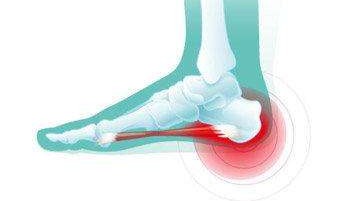

问答 网 : 骨刺微创手术一般一周左右就可以恢复的,如果骨刺出现在负重部位、关节内、腰椎椎管内都会引起疼痛等现象发生最多的部位是跟骨刺,由于跖筋膜老是紧张,引起周围水肿渗出,钙化形成骨刺,行走后经常挤压骨刺导致疼痛微创手术将骨刺切除,创口小,出血少Feb 17, 21 · 我妈妈患有足跟骨刺,能做微创手术痊愈吗人阅读问题描述:(女,21岁)我妈妈患有足跟骨刺,能做微创手术痊愈吗确定是骨刺能做微创手术吗Mar 08, 21 · 你好脚踝长骨刺如果保守治疗没有效果,这个就需要手术治疗,可以行关节镜微创治疗的,这个费用一般1万块钱左右的,平时注意多休息可以贴点膏药呀,啊,做些理疗和针灸这些治疗看看呢。

Jan 09, 15 · 跟痛症(跟骨骨刺、跖腱膜炎)的微创手术治疗:跟痛症只是一个总称,其病因、病理、发病机理目前尚未完全清楚。确认跟痛症首先必须排除跟骨骨髓炎、跟骨骨骺炎、骨结核、骨肿瘤等跟骨疾病,其一般特点是患者多为40岁以上的中老年人,男性较多,体型多比较肥胖Mar 12, 19 · 脚底有骨刺,需要去做手术吗? 如果走路功能受限,可以考虑微创手术治疗。骨刺是足部的保护性增生!不适随诊! 17 asky 追问 微创手术是大手术还是小手术,是要把骨刺磨掉吗? 脚踝骨刺,能切除手术吗患有骨刺,可以小针刀微创手术进行治疗,小针刀微创手术费用在百元左右 1449 相关问题 查看更多>> 你好骨刺手术得多少钱?

常见足跟痛的诊断与治疗要点 玖玖骨科 骨科医疗精准对接平台

足跟骨刺 快懂百科